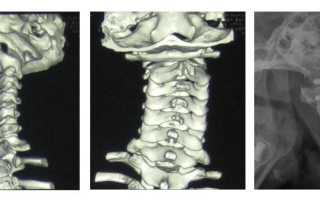

Анатомия шейных позвонков

Все эти отделы состоят из определённого количества позвонков, которые имеют особое строение. Не стал исключением и шейный отдел. Он состоит из семи позвонков (С1-С7), среди которых особенными считаются первый, второй и седьмой.

Первый позвонок (атлант или С1) имеет нетипичное строение относительно остальных. Он не имеет тела, остистого отростка и межпозвонкового диска. В его составе передняя и задняя дуги, которые соединяются по бокам с помощью костных утолщений. На задней дуге располагается отверстие, предназначенное для размещения зубовидного отростка следующего позвонка.

Строение 2 го шейного позвонка также уникально. Ещё его называют осевым позвонком или аксисом. Зубовидный отросток, расположенный на аксисе, крепится к атланту, тем самым позволяя человеку совершать разнообразные движения головой.

Анатомия первых двух позвонков не похожа на строение остальных. Атлант (первый позвонок или С1) имеет форму кольца. Своими плотными боковыми отделами он соединяется с затылочной костью. Аксис (второй позвонок или С2) имеет форму перстня. Передняя часть его снабжена отростком, выступающим кверху и скользящим по внутренней поверхности кольца атланта. Это сочленение называется суставом Крювелье. Причинами развития патологии у детей становится:

Рентгенография – это основной инструментальный метод, который позволяет определить подвывих. Исследование проводят в прямой и боковой проекции. При необходимости делаются снимки в косом положении, через рот, в состоянии сгибания/разгибания шеи. Рентген позволяет определить подвывих, его точное расположение, а также функциональные расстройства позвоночника.

С помощью КТ можно заметить, что высота межпозвонкового диска уменьшилась, а суставные поверхности сместились. При подвывихе атланта исследование покажет, что присутствует асимметрия между первым позвонком и зубовидным отростком второго.